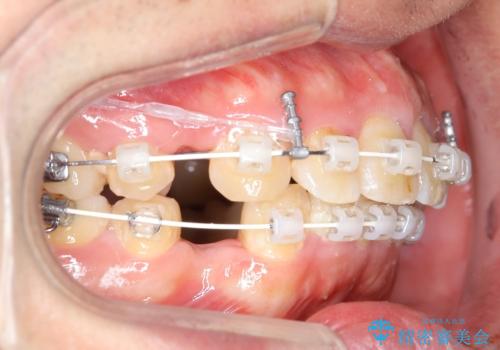

出っ歯、ガタつきの改善 ワイヤー矯正治療

- 上顎前歯の突出感と下顎前歯のガタつきが主訴で来院されました。

出っ歯とガタつきの改善を行うには抜歯が必要と診断し、上下左右第一小臼歯を抜歯する計画を立てました。

抜歯する事で歯の移動量が大きいことからワイヤー表側矯正装置で治療を行うことになりました。

今回のような歯の移動量が大きい場合、インビザライン治療では歯が傾いてしまう場合があります。

ワイヤー治療では歯の傾きを抑えながら大きい距離の移動が可能で、かみ合わせが深くなるリスクも少ないです。